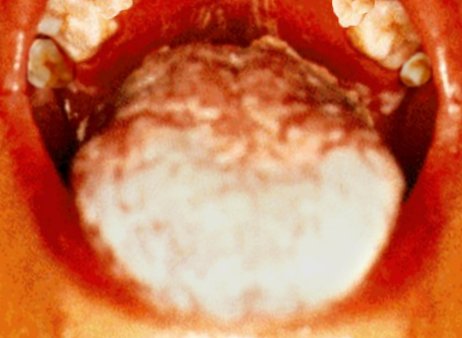

Afty v ústech

Pacientovo patro (nahoře) a jazyk (dole) ukazují příznaky aftů v ústech, příležitostné plísňové infekce

u pacienta.

S dalším oslabováním imunitního systému se můžou objevit vážné příznaky. Např. kožní vyrážka, horečka, únava, noční pocení, afty v ústech atd. Toto stadium nemoci se nazývá „symptomatická fáze HIV“. Tyto relativně lehké příznaky však budou nakonec následovány vážnými zdravotními problémy. Poslední stadium nemoci je obvykle „plně rozvinutý AIDS“. Imunitní systém selhal a v důsledku toho se může rozvinout jakékoliv množství nemocí. Např. pneumocistida, obzvláště závažná forma zápalu plic, tuberkulóza, Kaposiho sarkom, jinak vzácná forma rakoviny kůže, a různé jiné typy rakoviny, „chřadnutí“, tj. ztráta váhy, různé nemoci mozku, a mnohé další, které nakonec pacienta zabíjejí.